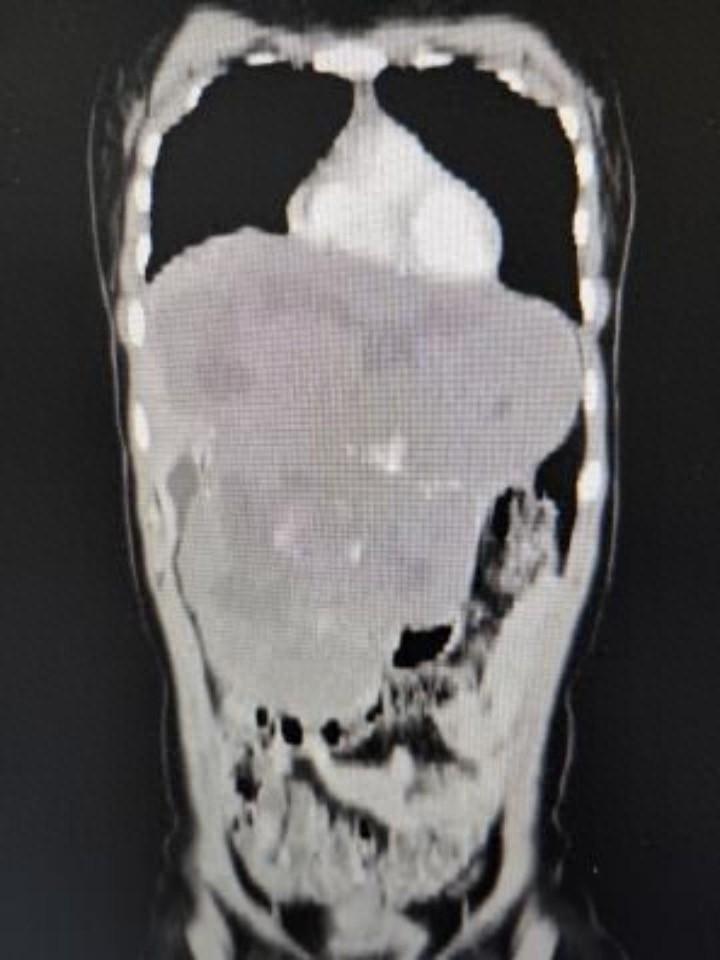

肝脏中常见的良性肿瘤——肝血管瘤,通常不威胁生命健康。但若肿瘤体积增至30cm×24.4cm×14.6cm,则会严重损害血液循环,压迫周边器官,并带来生命危险。李女士的病例生动地体现了这一罕见疾病的典型症状。

肝血管瘤主要因肝内血管过度扩张与生长所致。李女士的肿瘤体积大幅增长,濒临突破常规解剖限制,几乎触及腹腔容量上限。此巨型肿瘤不仅侵占腹腔空间,还对胃、肠等邻近器官施加压迫,不仅损害其功能,更可能引发器官移位或变形,进而加剧患者不适。

巨瘤对血流动力学产生显著扰动。肿瘤内部血管分布失衡,流速提升,这不仅加剧了肿瘤增大,且可能引发肿瘤破裂及出血,对患者生命构成威胁。因而,对于李女士而言,肿瘤不仅构成了生理上的负担,更是潜在的生命危险源。

经过周密策划与预案审核,由杨诏旭副主任领衔的包括范明、张小晶、郝晓坤、刘海旺等在内的医疗小组,迅速投入到一台极具挑战性的手术中。术中,在患者腹部壁下方成功建立了观察窗,内窥镜观察发现腹腔几乎被巨型血管瘤完全占据。因第一肝门受到严重压迫,手术区域非常狭小。